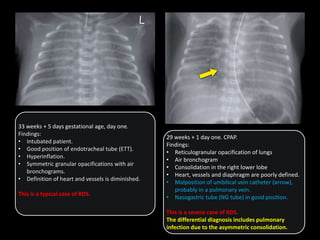

33 weeks + 5 days gestational age, day one.

Findings:

• Intubated patient.

• Good position of endotracheal tube (ETT).

• Hyperinflation.

• Symmetric granular opacifications with air

bronchograms.

• Definition of heart and vessels is diminished.

This is a typical case of RDS.

29 weeks + 1 day one. CPAP.

• Reticulogranular opacification of lungs

• Air bronchogram

• Consolidation in the right lower lobe

• Heart, vessels and diaphragm are poorly defined.

• Malposition of umbilical vein catheter (arrow),

probably in a pulmonary vein.

• Nasogastric tube (NG tube) in good position.

This is a severe case of RDS.

The differential diagnosis includes pulmonary

infection due to the asymmetric consolidation.